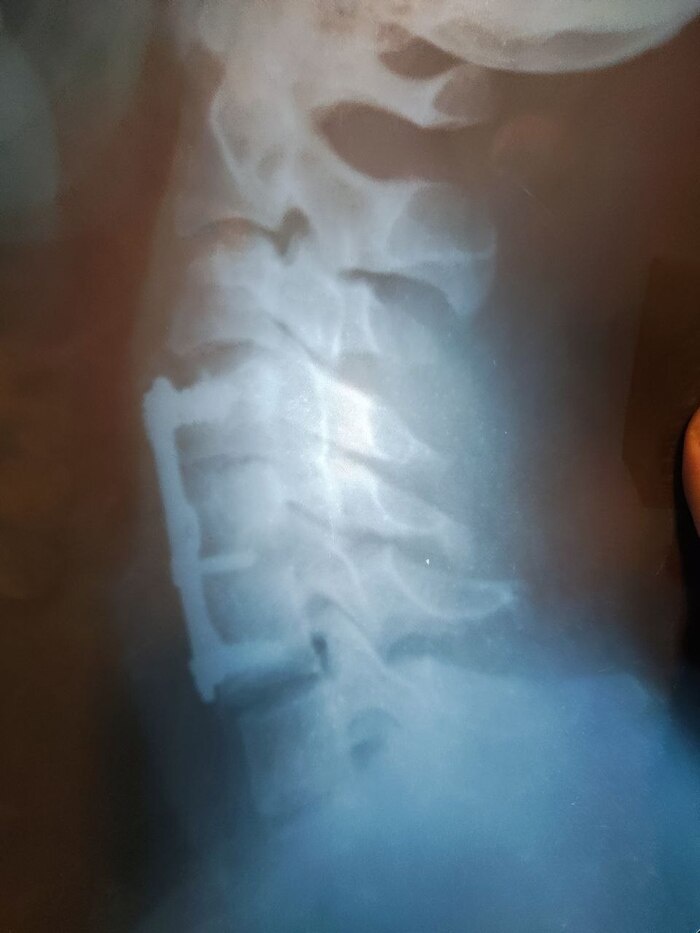

23 Года назад, нырнул в речку головой вперед - воткнулся в дно, услышал дикий хруст. Встал, плохо чувствую руки и шея болит. На следующий день, поехал с женой на рынок за продуктами и по пути заехали в больницу провериться. Сделали рентген и в перерыве до приема врача съездили на рынок, закупили 2 огромных пакета с продуктами (на следующий день у меня был день рождения). И вот я с двумя огромными пакетами в руках, в переполненном автобусе возвращаюсь в больницу. Врач смотрит снимок и говорит - "да вы в рубашке родились, а вас компресионно-осколочный перелом пятого шейного позвонка. Хорошо, что вы никак шею не беспокоили и тяжестей не носили, ложитесь к нам в нейрохирургию". Тут мне резко поплохело и я на негнущихся ногах пошел в палату, лег и старался даже дышать аккуратно часов 16 боясь. На следующий день, в свой день рождения, получил первый подарок - шейный фиксатор. Далее отцу пришлось ехать в Москву за титановой пластиной, потом два месяца ожидания (пока не дали главврачу взятку, места в графике на операцию не было) с постоянным ношением ошейника и наконец операция. Прошло 23 года, полет нормальный.